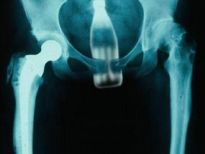

Şoke eden röntgen filmleri

Bu röntgen filmleri görenleri şaşkına çeviriyor!